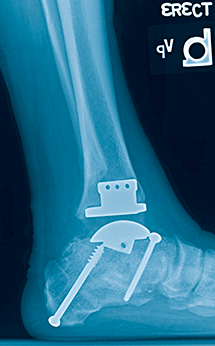

7 and 8

With the patient frustrated by the increasing stiffness and pain, we chose for takedown of the ankle fusion and revision subtalar fusion. The resected bone from the ankle arthroplasty provided ample bone graft for the subtalar fusion, and the improved motion spared the talonavicular joint from further stress.

The patient is now three years out from ankle replacement and is back to hiking in the woods recreationally.